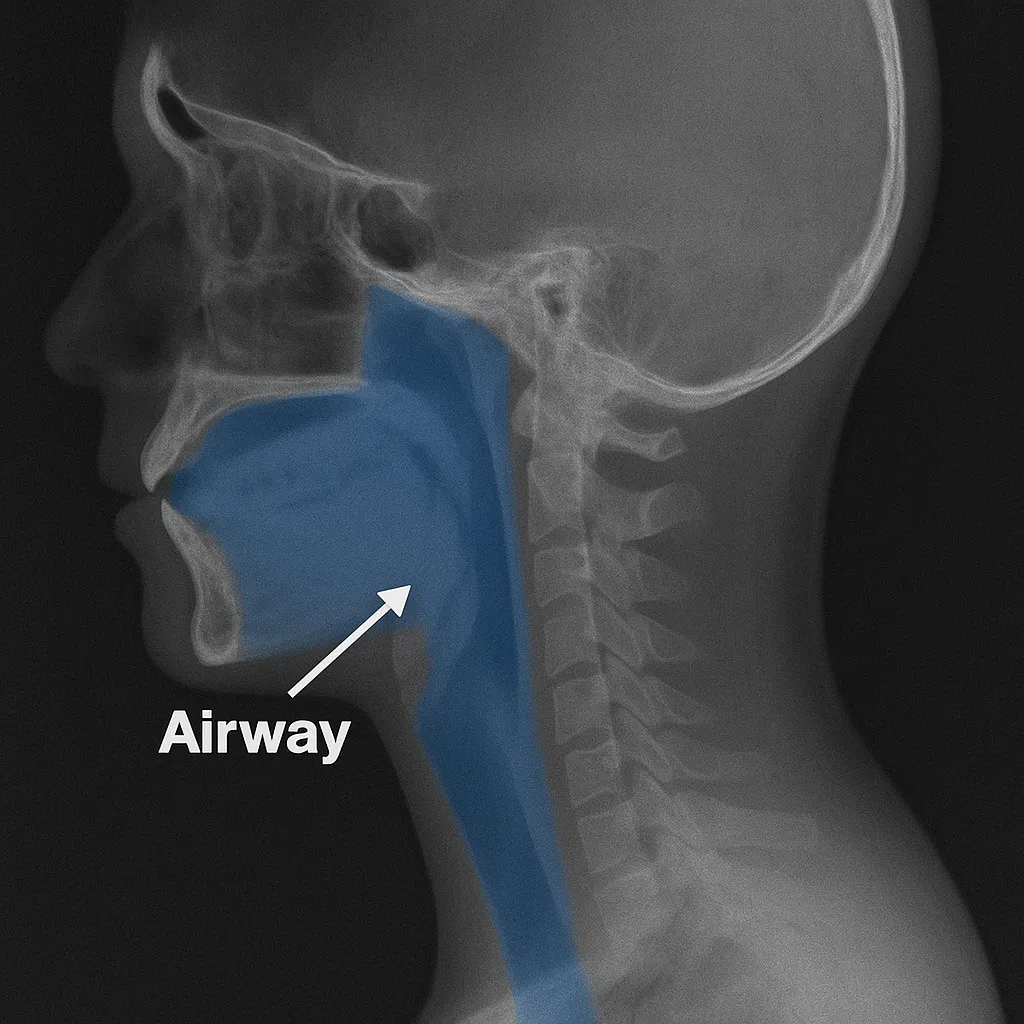

"Airway Dentistry" - let's unpack the latest trend in the dental profession.

Airway dentistry is not a recognized dental specialty and some of its proponents have problematic, non-evidence based treatment ideas.